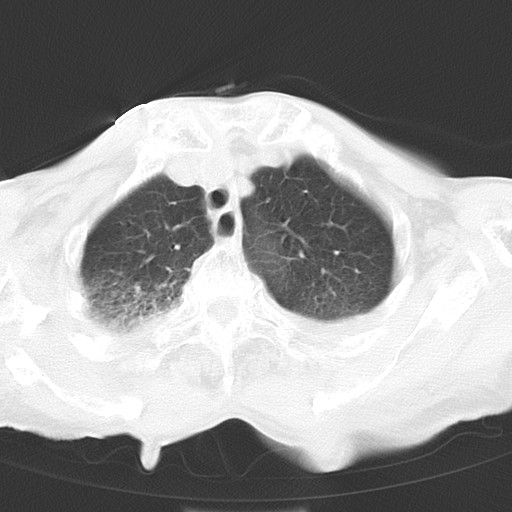

标题: CT21467:女,93岁,摔伤后检查。 [打印本页]

女,93岁,摔伤后检查。

右肺炎症,心功能不全伴双侧胸腔积液,右下肺膨胀不全,食管裂孔疝,冠脉钙化,心包少量积液,左侧肋骨骨折,请上传骨窗.

右侧锁骨\\肩胛骨骨折、右侧湿肺,心功能不全伴双侧胸腔积液,右下肺膨胀不全,左膈破裂或食管裂孔疝,冠脉钙化,心包少量积液,请上传骨窗.

右肺炎症,心功能不全伴双侧胸腔积液,右下肺膨胀不全,食管裂孔疝,冠脉钙化,心包少量积液,左侧肋骨骨折,右肩甲骨粉碎性骨折。93岁,高寿哇!